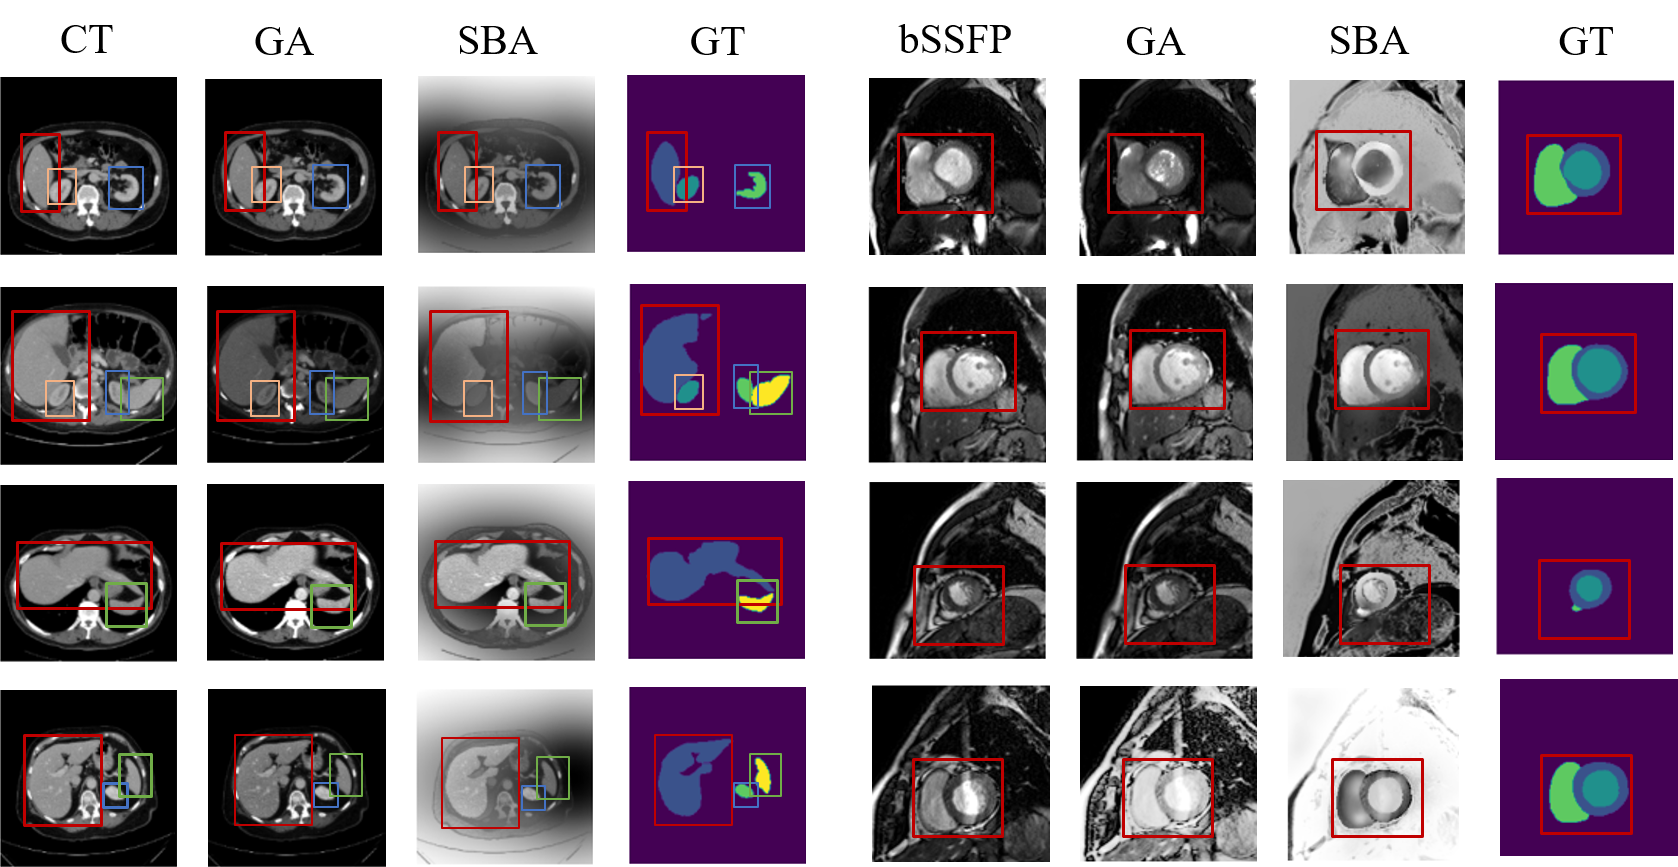

Fig. 5 illustrates the visual outputs of the GA and SBA data augmentation strategies. Changes in anatomical structural information are reflected in variations in organ shape, boundaries, and size within the images Yoon et al. (2024). The results demonstrate that our approach effectively preserves the anatomical structures of the organs to be segmented. Fig. 6 presents the GA, FA, and SBA results of FSDA-DG, along with segmentation results at 20% labeling rate. Saliency maps are also visualized to illustrate the model’s regions of focus. These results are obtained after applying weak data augmentation. The saliency maps show that activation regions effectively cover the target segmentation sites. The results of saliency maps demonstrate superior localization performance on the LGE and bSSFP modalities, which can be attributed to the relatively concentrated regions in the cross-sequence cardiac segmentation task. In contrast, for the abdominal dataset, where target organs are more spatially distributed, the saliency maps exhibit a broader focus across the image. More importantly, the final segmentation results remain accurate across the different augmentation strategies, demonstrating FSDA-DG’s ability to learn domain-invariant features and adapt to domain shifts.

To overcome the challenges of domain-biased learning and training instability with limited labeled data, we prioritize learning domain-invariant semantic features rather than simulating unseen domain distributions. We observe that explicit semantic knowledge for medical image segmentation exists in labeled data, and that the same anatomical regions exhibit class-level semantic consistency across domains. For example, as shown in Fig. 2, cardiac organs display strong semantic similarities across late gadolinium enhancement (LGE) and balanced steady-state free precession (bSSFP) imaging modalities. Domain shifts primarily arise from variations in pixel brightness mapping. These shifts can be modeled as linear combinations of (class number) random variables Su et al. (2023); Wang et al. (2024). Additionally, non-interest regions provide explicit information about domain distributions. Extracting invariant semantic information while accounting for explicit distributional interference is crucial for improving domain generalization ability. Inspired by this observation, we apply distinct data augmentation strategies for global images and focal regions (as shown in Fig. 2(b)). Global augmentation (GA) enriches explicit domain distribution information, while focal region augmentation (FA) simulates class-specific shifts to promote domain-invariant feature learning. This approach transforms limited annotations into extensive domain knowledge while preserving domain-invariant semantic information. To ensure augmented images align with real-world distributions, we introduce an augmentation scale-balancing mechanism (SBA) that uses saliency feature maps during training to correct augmented data. Unlike existing data augmentation-based DG methods that focus exclusively on global images, our approach expands the data distribution while preserving core regional semantic features, promoting domain-invariant feature learning under various perturbations.